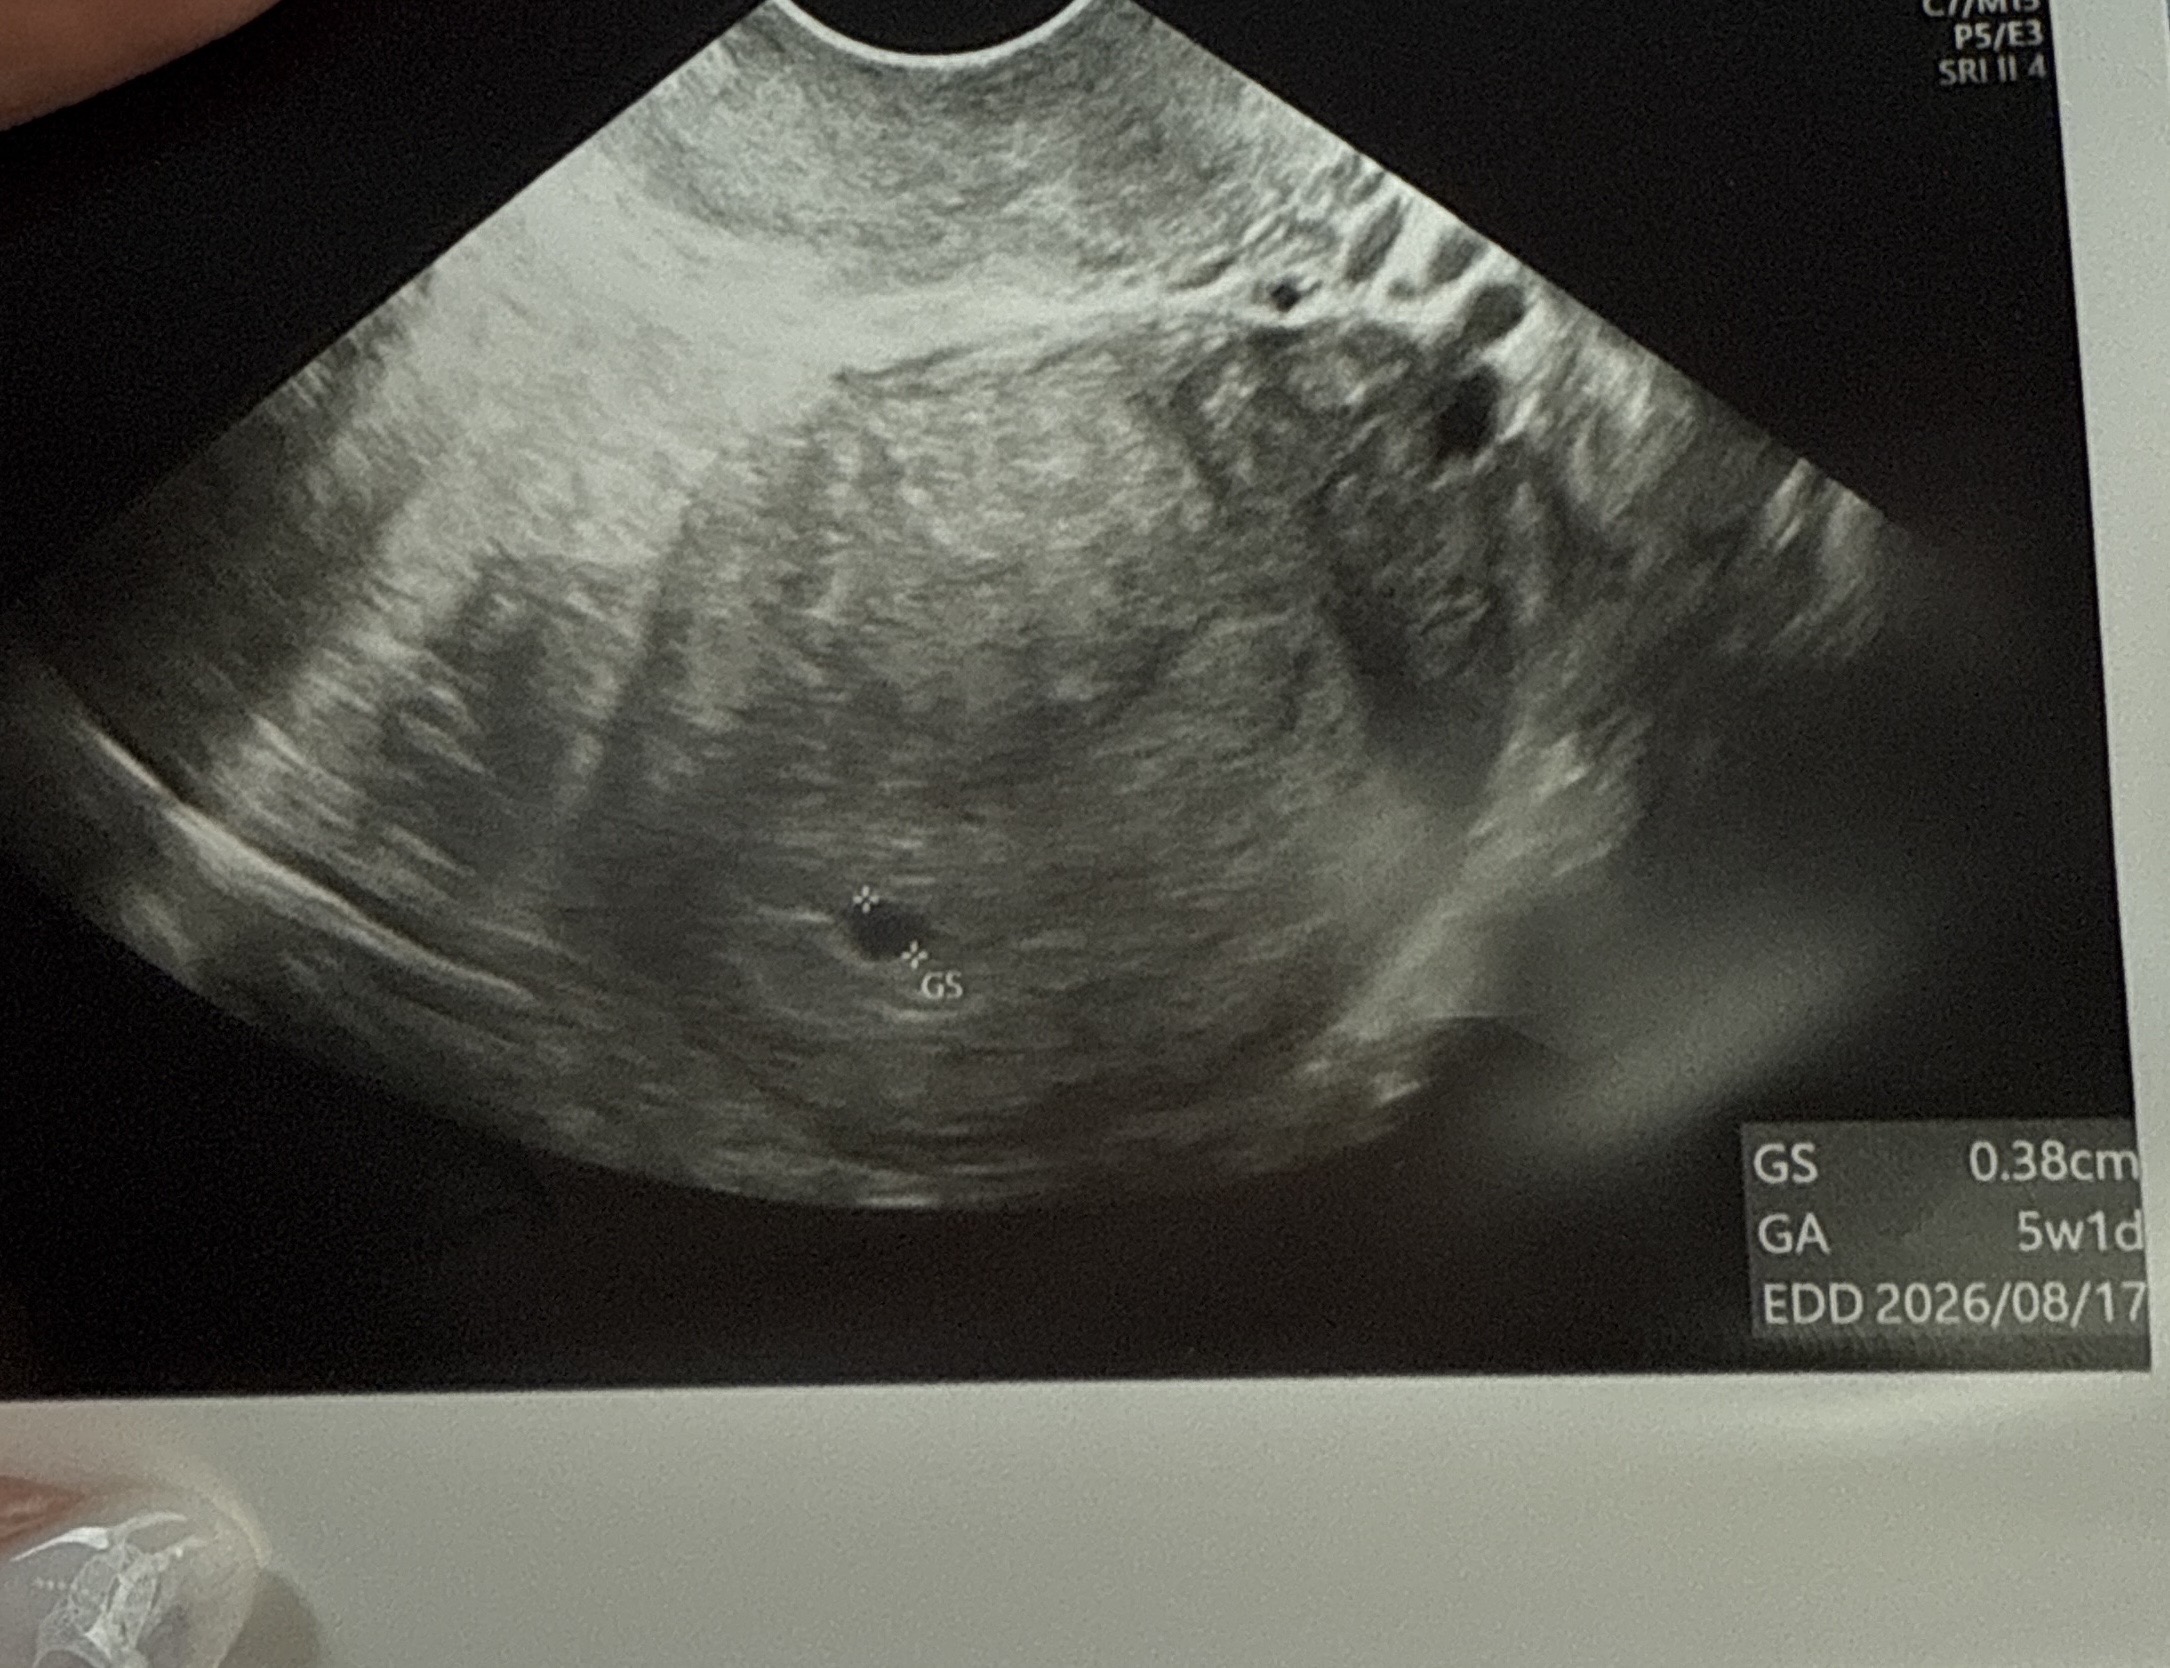

5주1일차 아기집크기봐주세요

10월달 소파술하고 두번째 천사가 왔어요 생리일기줌 오늘 6주 1일차인데 초음파는 5주 1일차였고 0.38cm인데 선생님은 주수에맞게 큰다고 다음주에 난황과 아기집이 잘 커있으면 된다 하더라구요ㅠ 다들 5주1일차 저처럼 아기집이 작았나요? 먼저 보내준 아기는 5주2일차때 0.64였어서 상대적으로 작게느겨져요ㅠ